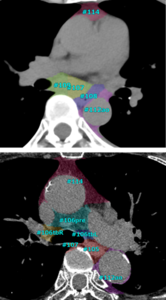

今回新たに搭載する「Body DWIビュー(MR)」は,こうした課題を解決し,WBDWI 読影の効率化を支援する機能である。本機能は,スティッチングやコントラスト補正を自動化することで,調整作業にかかる手間を軽減する。さらに,MRIの三次元セグメンテーション技術とDWI解析を組み合わせることで,骨領域のみに,ADCカラーマップ表示*10を行うことができ,骨転移箇所探索の支援につながることが期待できる。

骨抽出機能の例。骨転移検索目的での読影効率化に繋がることが期待できる。